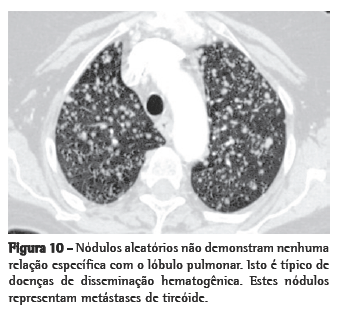

Random nodules

Random nodules are defined by their seemingly haphazard occurrence in

peribronchovascular regions, interlobular septa, and pleura, without a consistent perilymphatic pattern and absence of a consistent relationship with the secondary pulmonary lobule. An HRCT image from a patient with hematogenous metastases from thyroid cancer is shown in Figure 10.